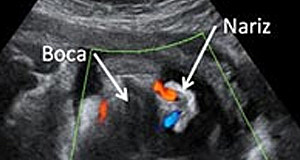

El embrión mide entre 2 y 3 centímetros en la semana 9 de embarazo y su forma ya es mucho más parecida a un ser humano: Aparecen las manos con los dedos y las muñecas, Las piernas se alargan aparecen los pies con sus dedos correspondientes. La cabeza sigue siendo la parte más grande en proporción con el resto del cuerpo los párpados cubren parcialmente los ojos. Los pabellones auriculares están bien formados. La boca se aprecia e incluso se abre.

Con 25 semanas de embarazo tu bebé pesa ya 700 gramos y mide 22 centímetros desde la cabeza al final de la columna en la semana 25 de embarazo. La razón es que el bebé todavía es pequeño y tiene espacio suficiente para moverse y cambiar de posición varias veces durante el día. Los párpados del niño se abren y se pueden ver los ojos. La lengua sale de la boca y se mueve hacia los lados. Tu hijo bosteza, sonríe y empieza a hacer gestos como si de un niño mayor se tratase.